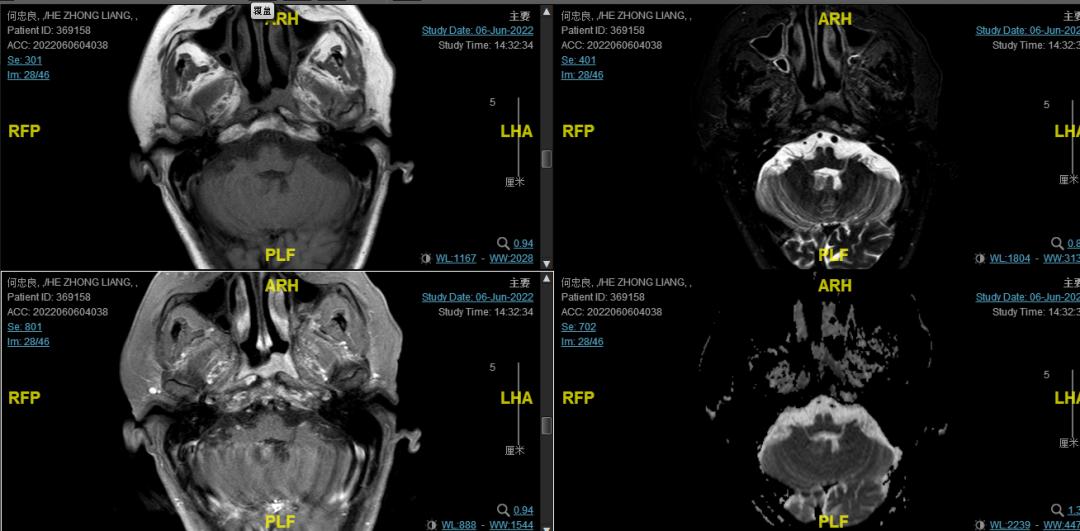

后患者至江苏省肿瘤医院放疗科就诊,2022-06-06完善头颅MR检查:

修正诊断: 鼻咽癌T3N1M0,Ⅲ期。